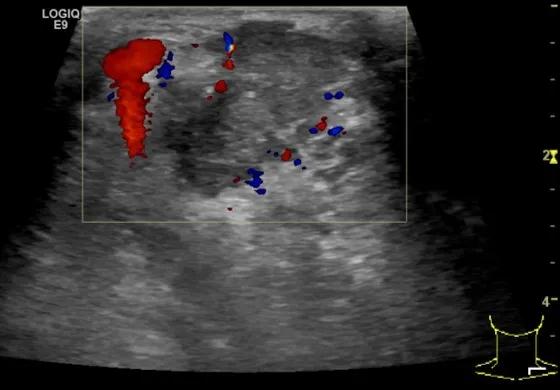

第二例是食管癌患者,术后半年余锁骨上固定淋巴结可触及肿大,疼痛非常明显,系统治疗后无缓解,患者希望通过局部处理缓解症状。造影显示强化信号明显,结节部分区域坏死,故主要针对强化区域从后向前的逐层的消融,皮下进行液体隔离减少烫伤。热消融后影像显示血流增强消失,弹性、硬度增高,一个月后复查显示充盈缺损,完全消融,疗效远超预期。

(病例2图例)